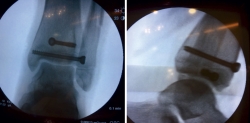

Tras conseguir una adecuada reducción de la fractura, realizamos fijación interna con 2 tornillos canulados de rosca parcial de 16 mm (un tornillo epifisario de lateral a medial y otro metafisario anteroposterior) comprobando bajo fluoroscopio la reducción de la fractura (Figura 5).

Figura 5. Control radiológico intraoperatorio: fijación con tornillos canulados.